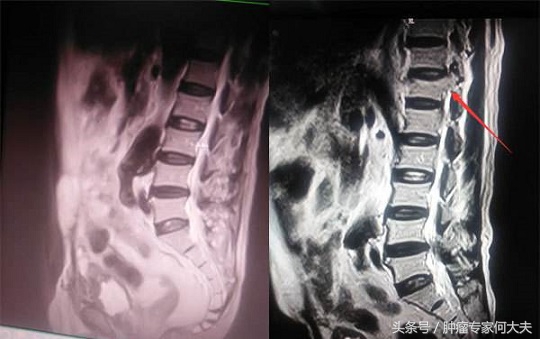

2015年9月患者腿疼、腰疼,全身骨扫描提示右侧股骨、腰椎、胸骨等多发骨转移,进一步相应部位的核磁检查提示骨质破坏严重,此时再继续服用克唑替尼的基础上,每月增加一次唑来膦酸抗骨转移治疗。间断服用泰勒宁等镇痛药物患者疼痛控制尚满意,但是老太太骨转移后生活质量明显下降,此后的生活基本上已卧床为主。但食欲一切都好。